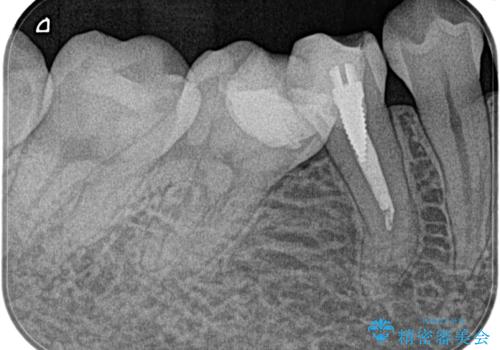

【湾曲根管】奥歯がズキズキ痛い

- 奥歯が1週間前からズキズキ痛いことを主訴に来院されました。

診査の結果、不可逆性歯髄炎と診断し抜髄処置を行っております。

【使用ファイル】NEX-MS

【充填法】Hydraulic Condensation